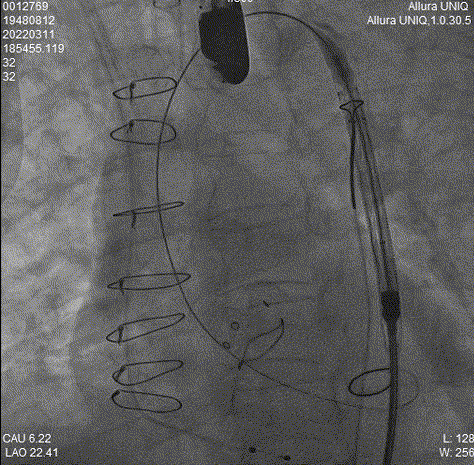

对侧Snare辅助

Snare辅助过弓